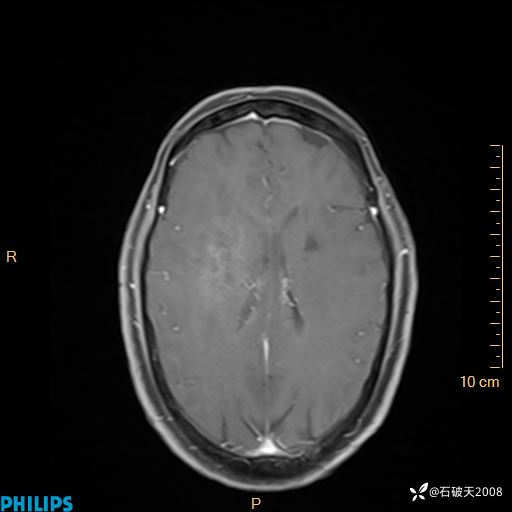

2024.2.21MR

增强轴位